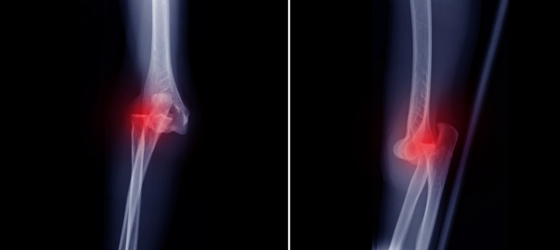

No es un simple “hueso fuera de lugar” Es común confundir esto con una “luxación de rótula” (cuando el pequeño hueso frontal se desplaza, algo frecuente y menos grave). La luxación traumática es un evento de alta energía que causa la separación completa del fémur y la tibia, destruyendo ligamentos, nervios y vasos sanguíneos críticos.

Una verdadera emergencia médica Esta lesión representa una urgencia vascular ortopédica severa debido a:

- Daño vascular: La arteria poplítea se desgarra en casi el 50% de los casos.